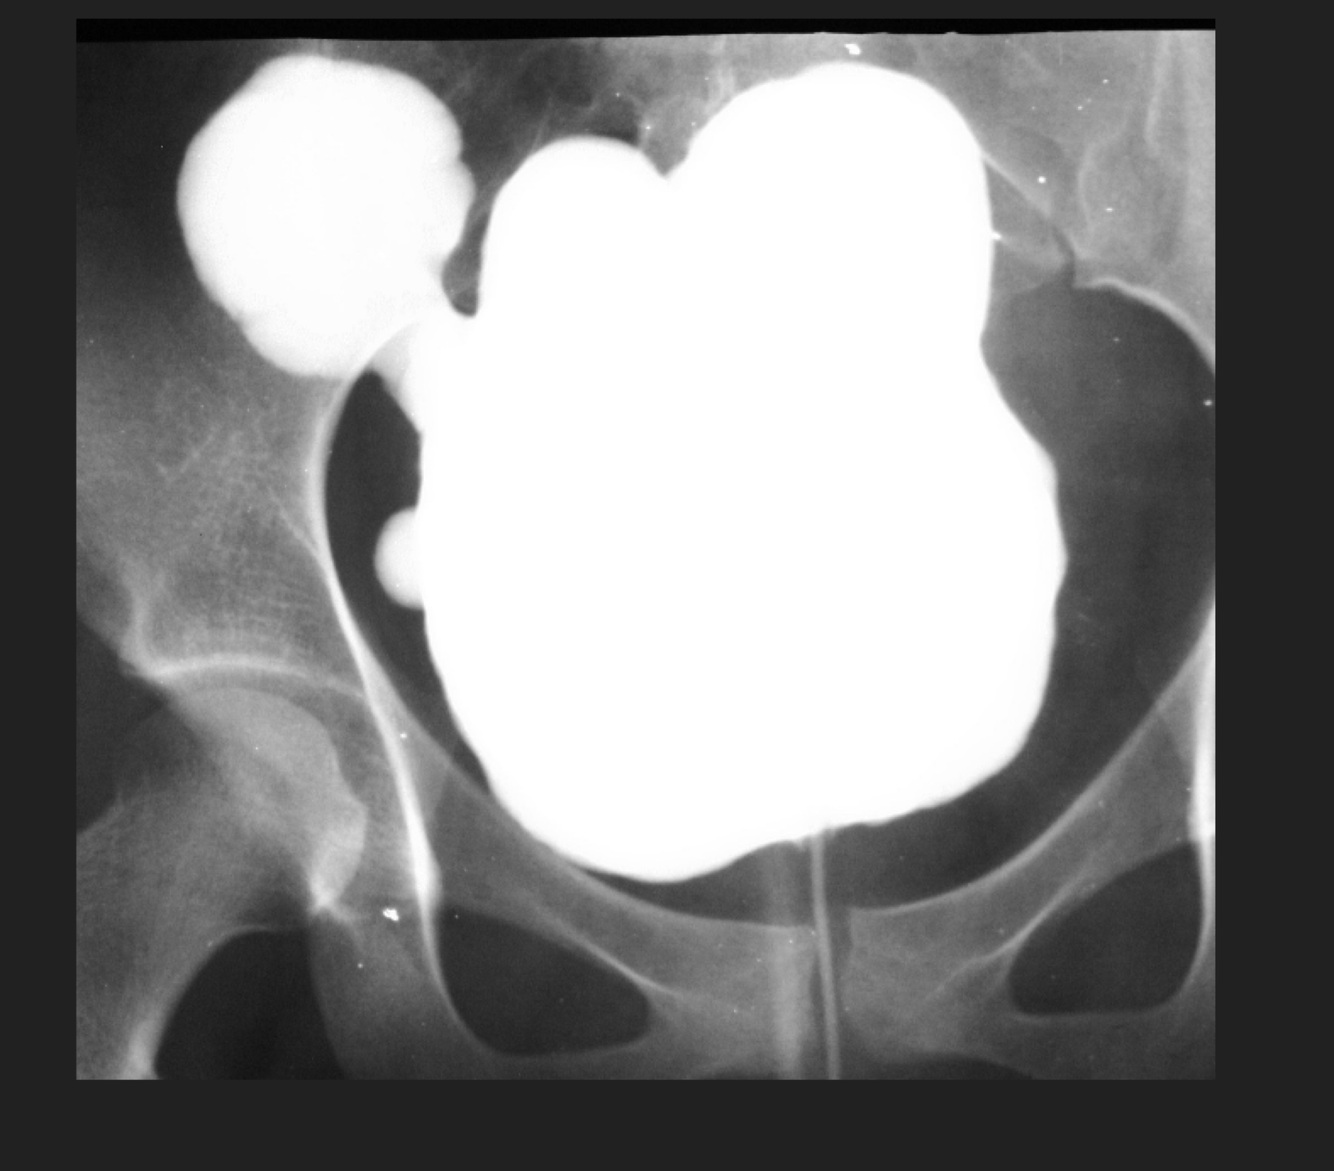

3

Q

Cistograma con datos de:

A

Divertículos vesicales

How well did you know this?